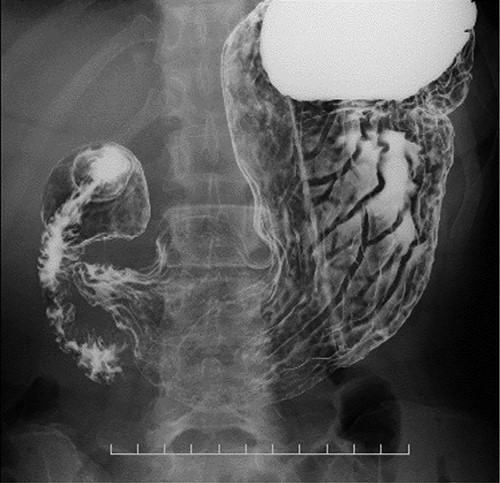

Upper gastrointestinal series showing the stomach; there were no specific findings in the stomach.

Preoperative computed tomography (CT) and barium meal studies were performed. The CT findings showed circumferential wall thickening with infiltrative change at the middle of the intrathoracic esophagus, with luminal dilation of the oral side of the stenotic esophagus (Figs 2, 3). The barium meal study showed no abnormal findings in the stomach (Fig. 4). Thoracoscopic esophagectomy was performed with the patient in the semi-prone position, followed by esophageal reconstruction using a gastric tube with the patient in the supine position. The operation was started with bilateral lung ventilation using a single-lumen endotracheal tube. A four-port thoracoscopic technique was used as follows: an observation port with a 10-mm scope was placed at the ninth intercostal space at the line of the inferior scapular angle, and two 5-mm ports and one 12-mm port for the intrathoracic procedures were placed at the third, fifth and seventh intercostal spaces, respectively, at the posterior axillary line (Fig. 5). Pneumothorax was created using 10 mmHg of CO2 to deflate the lung to achieve a better operative field. The pleura and connective tissue around the thoracic esophagus showed severe inflammatory and fibrotic changes. In particular, the middle thoracic esophagus was strongly adherent to the arch of the azygos vein and the tracheal bifurcation.